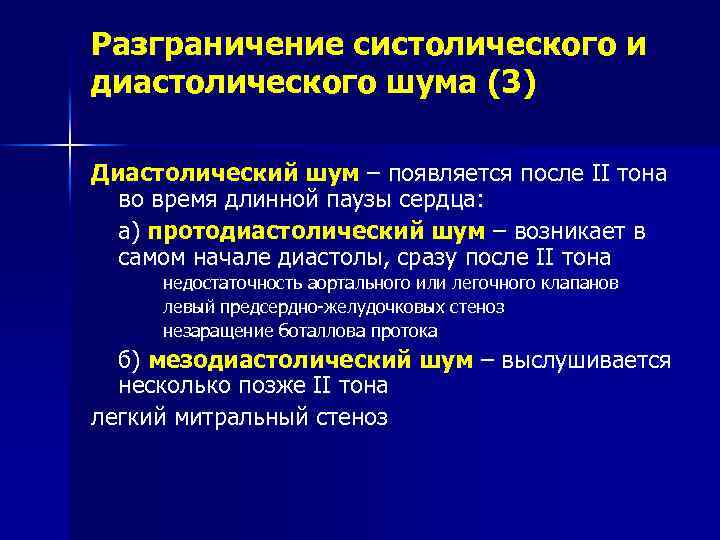

Разграничение систолического и диастолического шума (3) Диастолический шум – появляется после II тона во время длинной паузы сердца: а) протодиастолический шум – возникает в самом начале диастолы, сразу после II тона недостаточность аортального или легочного клапанов левый предсердно-желудочковых стеноз незаращение боталлова протока б) мезодиастолический шум – выслушивается несколько позже II тона легкий митральный стеноз